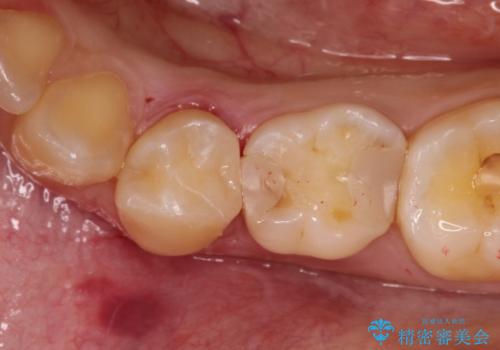

【セラミックインレー】虫歯の治療

- 定期検診にてむし歯を認めたため、セラミックインレーにて修復を行いました。

e-max プレスインレーにて修復治療を行っているため適合性及び審美性の高い治療を行うことができます